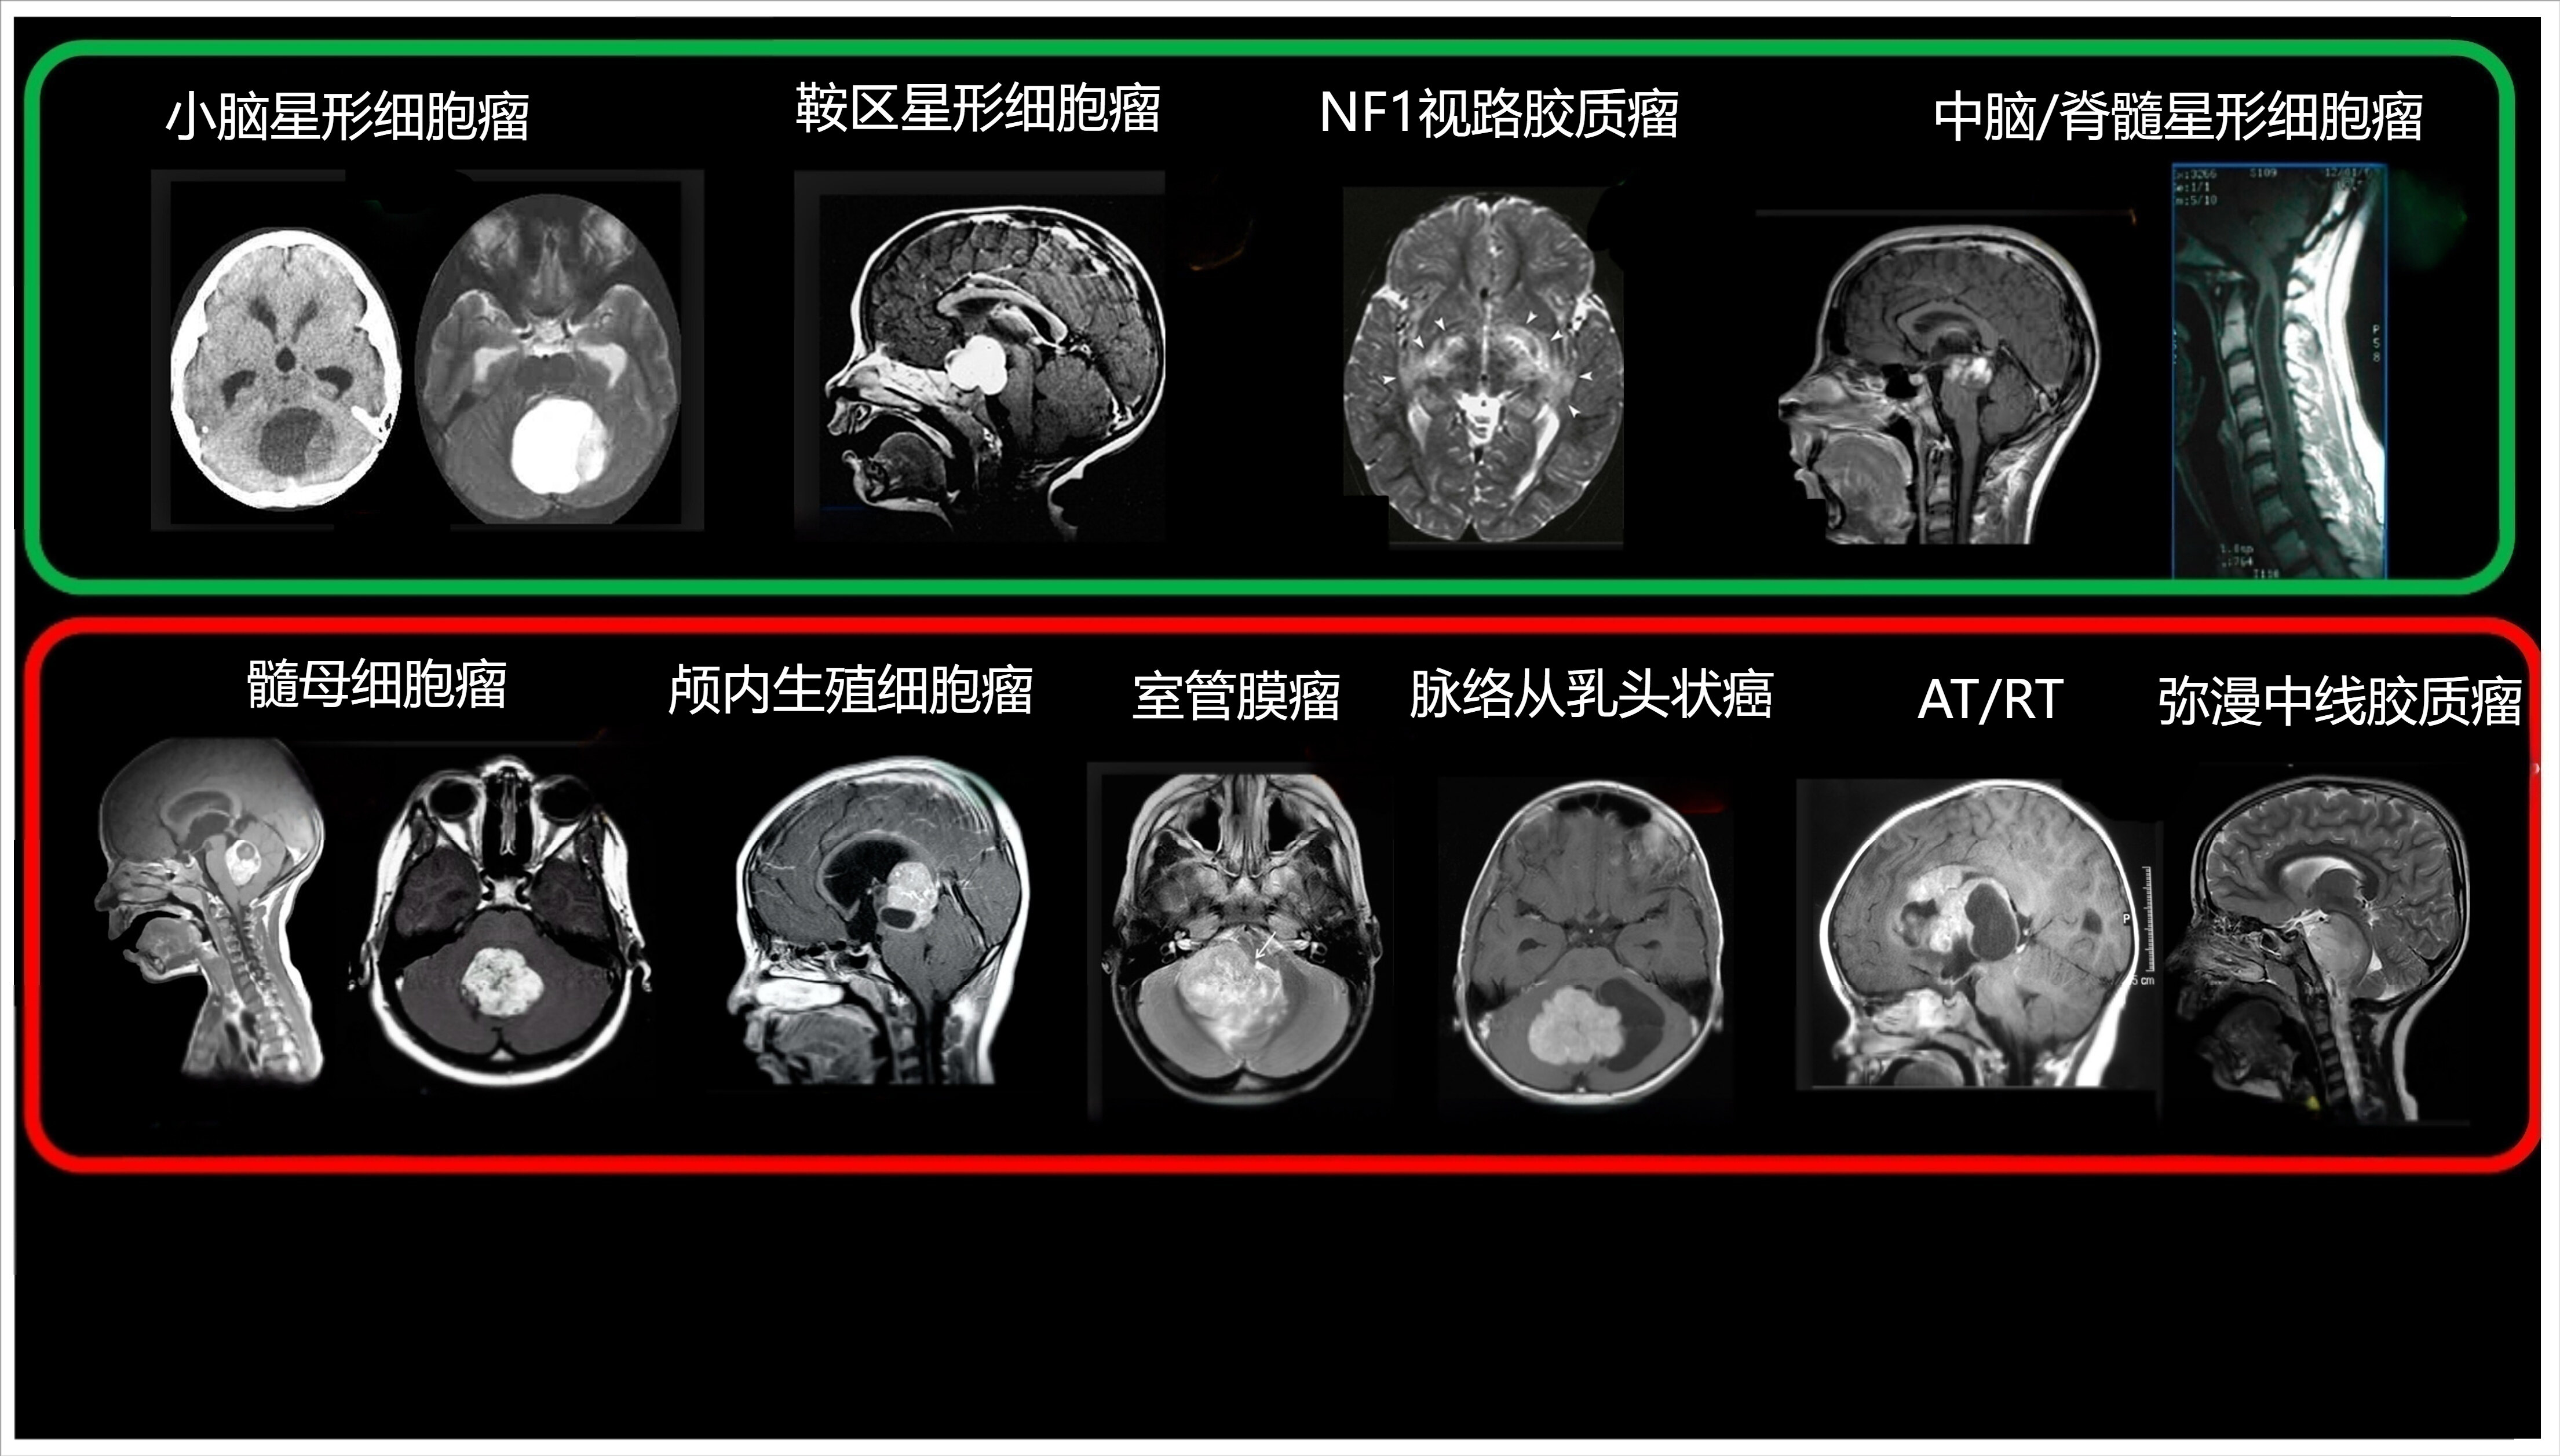

1.什么是兒童腦腫瘤?兒童腦腫瘤是兒童常見的實(shí)體腫瘤之一,僅次于白血病。由于兒童的大腦仍處于發(fā)育階段,腦腫瘤不僅影響神經(jīng)功能,還可能對認(rèn)知、運(yùn)動(dòng)和生長發(fā)育造成長期影響。因此,早期發(fā)現(xiàn)和精準(zhǔn)治療對于提高兒童腦腫瘤的治愈率和生活質(zhì)量至關(guān)重要。近年來,隨著精準(zhǔn)醫(yī)學(xué)、分子靶向治療的發(fā)展,兒童腦腫瘤的治療取得了重要突破,部分高?;颊叩纳嫫陲@著延長,新的治療策略也在不斷優(yōu)化。2.兒童腦腫瘤的流行病學(xué)兒童腦腫瘤的發(fā)生率因國家和地區(qū)不同而略有差異。根據(jù)全球癌癥流行病學(xué)數(shù)據(jù):兒童腦腫瘤的總發(fā)生率約為每年每10萬兒童中4.6-5.7例,是兒童最常見的實(shí)體惡性腫瘤,占所有兒童癌癥的15%-20%。年齡分布:兒童腦腫瘤可發(fā)生于任何年齡段,但在5-9歲年齡組較為常見。性別分布:總體來看,男孩的發(fā)病率略高于女孩,但具體到不同類型的腦腫瘤,性別差異可能有所不同。例如,髓母細(xì)胞瘤(MB)更常見于男孩,而生殖細(xì)胞瘤(Germinoma)在男孩中遠(yuǎn)高于女孩。病理類型:低級別膠質(zhì)瘤(LGG)(如毛細(xì)胞型星形細(xì)胞瘤):占所有兒童腦腫瘤的約40%,是最常見的類型。高級別膠質(zhì)瘤(HGG)(如彌漫性中線膠質(zhì)瘤):惡性程度高,治療難度大,生存率低。髓母細(xì)胞瘤(MB):占兒童中樞神經(jīng)系統(tǒng)惡性腫瘤的15-20%,是最常見的惡性腦腫瘤。室管膜瘤(Ependymoma):占5-10%,好發(fā)于第四腦室。生殖細(xì)胞瘤(Germinoma):多見于松果體區(qū)和鞍上區(qū),占3-5%。胚胎性腫瘤(EmbryonalTumors):如非典型畸胎樣/橫紋肌樣瘤(AT/RT),常見于3歲以下兒童,侵襲性極強(qiáng)。兒童腦腫瘤的流行病學(xué)特征顯示,其發(fā)病率與遺傳因素、環(huán)境暴露(如電離輻射)等多種因素相關(guān),但確切的病因尚不完全明確。精準(zhǔn)診斷和個(gè)體化治療是改善兒童腦腫瘤預(yù)后的關(guān)鍵。3.兒童腦腫瘤的臨床表現(xiàn)兒童腦腫瘤的癥狀與腫瘤的部位、大小、病理類型及生長速度有關(guān)。由于兒童的顱骨尚未完全閉合,部分患兒早期癥狀可能較隱匿,需特別關(guān)注以下癥狀:3.1顱內(nèi)壓增高癥狀由于腫瘤占位導(dǎo)致腦脊液循環(huán)受阻或直接壓迫腦組織,常表現(xiàn)為:頭痛(尤其是清晨或夜間加重)嘔吐(常為噴射狀,且與進(jìn)食無關(guān))視乳頭水腫(眼底檢查可見)精神狀態(tài)改變(如易怒、嗜睡、注意力下降)3.2神經(jīng)系統(tǒng)局灶性癥狀腫瘤侵犯特定腦區(qū)時(shí)可能出現(xiàn)相應(yīng)的功能障礙:小腦腫瘤:步態(tài)不穩(wěn)、共濟(jì)失調(diào)、眼球震顫腦干腫瘤:面癱、吞咽困難、復(fù)視丘腦或基底節(jié)區(qū)腫瘤:對側(cè)肢體無力或運(yùn)動(dòng)障礙枕葉腫瘤:視野缺損、視覺異常3.3癲癇發(fā)作部分低級別膠質(zhì)瘤或皮質(zhì)部位的腫瘤可引發(fā)癲癇,表現(xiàn)為:局灶性癲癇(單側(cè)抽搐、意識(shí)清晰)全身性癲癇(意識(shí)喪失、全身抽搐)3.4頭圍增大(嬰幼兒)由于嬰幼兒囟門未閉合,顱內(nèi)壓增高可表現(xiàn)為頭圍異常增大??砂橛星柏堵∑稹㈧o脈怒張、日落征(眼球下轉(zhuǎn)受限)。3.5內(nèi)分泌異常垂體或松果體腫瘤可引起生長遲緩、性早熟或尿崩癥。生殖細(xì)胞瘤常導(dǎo)致青春期提前(男孩多見)。4.兒童腦腫瘤的影像學(xué)檢查方法磁共振成像(MRI)首選檢查,可清晰顯示腫瘤位置、大小、邊界及對周圍結(jié)構(gòu)的影響。增強(qiáng)MRI(靜脈注射對比劑)可幫助鑒別低級別vs高級別腫瘤。計(jì)算機(jī)斷層掃描(CT)適用于急性顱內(nèi)高壓時(shí)的初步篩查(如出血、鈣化)。松果體區(qū)腫瘤常伴鈣化,CT較MRI更容易發(fā)現(xiàn)。5.兒童腦腫瘤的常見類型5.1低級別腦腫瘤毛細(xì)胞型星形細(xì)胞瘤(PilocyticAstrocytoma,PA)最常見的兒童低級別腦腫瘤,主要發(fā)生于小腦、視神經(jīng)膠質(zhì)瘤、丘腦或腦干。生長緩慢,邊界清晰,手術(shù)切除率高,預(yù)后良好,大多數(shù)病例通過手術(shù)可實(shí)現(xiàn)長期無復(fù)發(fā)生存。BRAF基因異常(V600E突變和BRAF融合):BRAFV600E突變→推薦BRAF+MEK抑制劑聯(lián)合治療(達(dá)拉非尼+曲美替尼)。BRAF融合(KIAA1549-BRAF)→以手術(shù)治療為主,必要時(shí)可使用MEK抑制劑(曲美替尼),避免使用BRAF抑制劑發(fā)育不良性神經(jīng)上皮腫瘤(DNET)多見于兒童和青少年,常伴有癲癇發(fā)作。主要位于顳葉,手術(shù)切除后癲癇癥狀可明顯改善。脈絡(luò)叢乳頭狀瘤(ChoroidPlexusPapilloma,CPP)主要發(fā)生于側(cè)腦室、四腦室,可引起腦積水。完全切除可治愈,無需額外放療或化療。5.2高級別腦腫瘤(生長快,侵襲性強(qiáng))髓母細(xì)胞瘤(Medulloblastoma)最常見的兒童惡性腦腫瘤,起源于小腦,易沿腦脊液播散至全腦脊髓。根據(jù)分子分型不同(WNT、SHH、Group3、Group4),對放化療的敏感性不同。治療方案:手術(shù)+放療+化療。室管膜瘤(Ependymoma)多見于四腦室、脊髓,部分具有侵襲性,手術(shù)切除后容易復(fù)發(fā)。復(fù)旦大學(xué)附屬兒科醫(yī)院正在開展PFA型室管膜瘤的PARP抑制劑臨床試驗(yàn),初步顯示良好的療效。彌漫性中線膠質(zhì)瘤(DMG,原DIPG)高度侵襲性,幾乎無法手術(shù),預(yù)后極差。主要發(fā)生于腦干(腦橋)、丘腦和脊髓中線區(qū)域。H3K27M突變患者可考慮EZH2抑制劑靶向治療。復(fù)旦大學(xué)附屬兒科醫(yī)院神經(jīng)外科正在開展基于γ-H2AX高表達(dá)的DMG運(yùn)用PARP抑制劑的靶向治療,初步研究表明該方法在提高治療反應(yīng)率、延長生存期方面優(yōu)于傳統(tǒng)治療方法。PARP抑制劑通過干擾腫瘤細(xì)胞的DNA修復(fù)機(jī)制,誘導(dǎo)細(xì)胞凋亡,尤其適用于γ-H2AX陽性表達(dá)的DMG患者,為這一極具挑戰(zhàn)性的腫瘤類型帶來了新的治療希望兒童彌漫性高級別膠質(zhì)瘤(HGG)包括膠質(zhì)母細(xì)胞瘤(GBM),生長迅速,治療難度大。部分IDH1/IDH2突變患者可使用IDH抑制劑靶向治療。復(fù)旦大學(xué)附屬兒科醫(yī)院神經(jīng)外科正在開展基于γ-H2AX高表達(dá)的兒童彌漫性高級別膠質(zhì)瘤(HGG)靶向治療研究。初步研究顯示,PARP抑制劑的療效優(yōu)于傳統(tǒng)治療方案,可延長生存期并改善患者生活質(zhì)量,為難治性兒童HGG提供了新的治療方向。非典型畸胎樣/橫紋肌樣瘤(AT/RT)侵襲性極強(qiáng),多見于3歲以下兒童。需手術(shù)+放療+化療聯(lián)合治療,部分患者可嘗試EZH2抑制劑。6.結(jié)論兒童腦腫瘤的治療進(jìn)入精準(zhǔn)醫(yī)學(xué)時(shí)代,通過基因檢測+靶向治療+個(gè)體化放化療的綜合策略,許多患兒的生存率得到提高。復(fù)旦大學(xué)附屬兒科醫(yī)院等權(quán)威機(jī)構(gòu)正在探索新型靶向藥物,如PARP抑制劑用于室管膜瘤和γ-H2AX高表達(dá)腫瘤,為兒童腦腫瘤患者帶來新希望。家長和醫(yī)生應(yīng)密切關(guān)注最新治療進(jìn)展,結(jié)合個(gè)體化診療方案,為患兒爭取最佳治療效果。